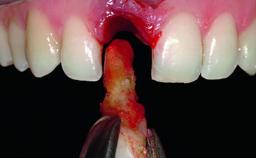

A 49-year-old female patient was referred for implant therapy to replace the upper right central incisor (tooth 11). The tooth had been assessed by an endodontist who diagnosed a vertical fracture of the root. The tooth had a hopeless prognosis and needed to be extracted. The patient was healthy and was not taking any medications. She was allergic to penicillin. The patient had high esthetic demands but her expectations were realistic. The extraoral examination revealed no facial asymmetries. The right temporomandibular joint demonstrated an opening click but was otherwise asymptomatic. The lip line was high with a significant gingival display.